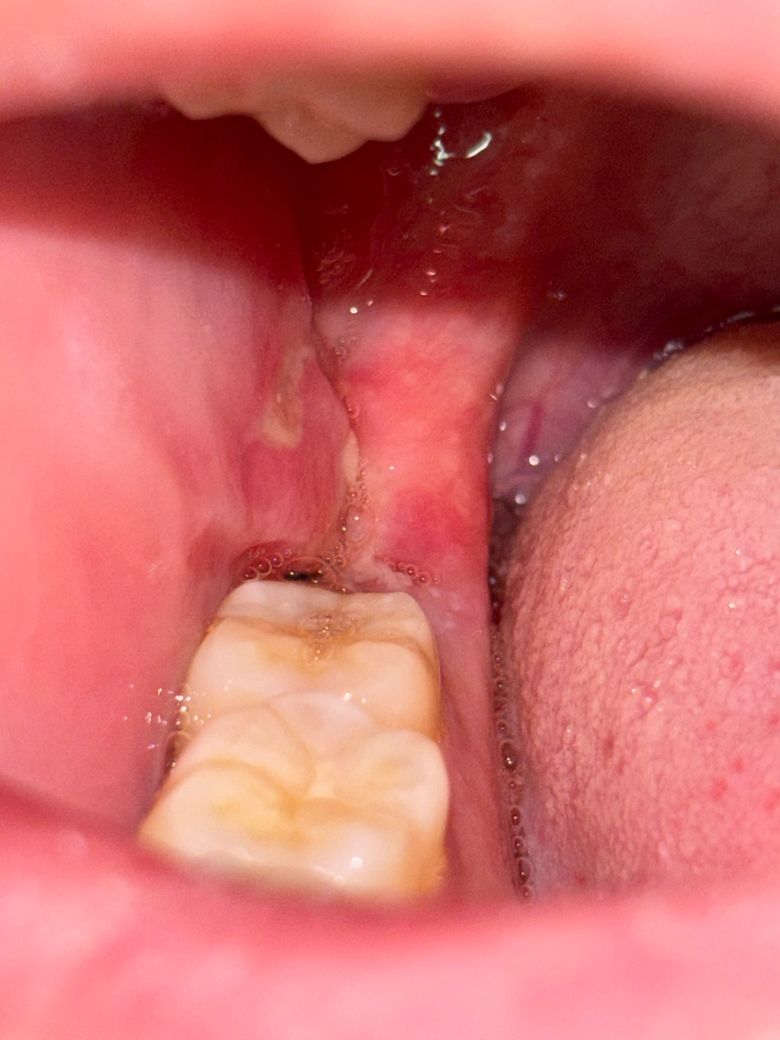

사랑니 발치 후 입안 염증이 심해졌어요

목요일에 사랑니를 발치하고 어제부터 입안 염증이 심져서 음식 씹거나 말하는 게 너무 힘듭니다.ㅜ

사진상의 흰색부분이 길게 났는데 구내염인건가요? 잇몸이 아프다기보단 뭔갈 씹을 때 계속 저기가 닿아서 아픈 것 같아요

그리고 볼 쪽 살이랑 잇몸 절개부위가 (원랜 저기에 선이 있었습니다) 붙어버린 것처럼 보이는데 괜찮은 걸까요…?? ㅜㅜ

구내염은 아니고 사랑니 발치를 하면서 잇몸 절개를 한부위 잇몸이 아물면서 생기는 현상입니다. 크게 걱정은 안하셔도 될것같습니다.

염증 양상이 다소 있긴 합니다만 크게 치유에 문제가 있어보이진 않습니다. 해당 부위 자극가지 않도록 주의해주시기 바랍니다.

사랑니를 발치하고 나면 발치한 부위에 상처가 생길수 있습니다. 크게 문제가 되는것은 아니며 상처가 난 잇몸은 보통 2주정도 지나면 아물게 됩니다.